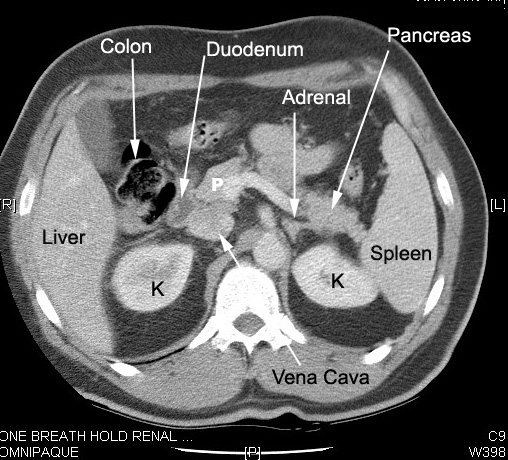

Normal kidney in CT:

Located in  retro peritoneum surrounded by fat.

Renal cortex enhances with IV contrast.

In the nephrographic phase the contrast has not been excreted and the renal pelvis appears dark.

Renal pelvis and ureters can be seen as the contrast is excreted by kidneys.

Note the relationship of kidneys

Renal veins drain into IVC.